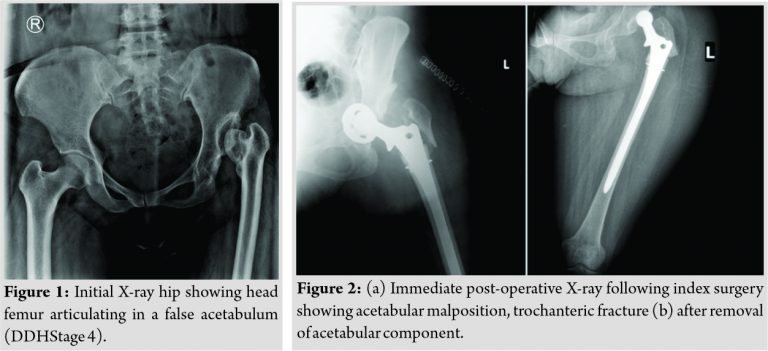

A 32-year-old female reported to us with pain, limp, and shortening of the left lower limb. The patient was on traction for the left lower limb. The previous records revealed that patient was operated for DDH 4 Left hip (Crowe’s Classification) at some other institute 3 weeks ago (Fig.1). During surgery eccentric reaming of acetabulum resulted in medial and posterosuperior acetabular wall defects. An uncemented metal backed cup was used on acetabular side and Corail stem was used for femoral side. Difficulty in achieving on table reduction of hip during surgery led surgeon to explant Corail stem and take a lower neck cut. However, this resulted in iatrogenic trochanteric fracture. Due to lack of proximal support in femur, Corail Stem(Depuy) was exchanged for distal fitting Solution stem (Depuy). Meanwhile acetabular component migrated medially which went unnoticed during surgery and was detected on postoperative X-rays (Fig. 2a).The acetabular component was removed by primary surgeon at subsequent surgery while femoral stem was retained in situ. Postoperatively, patient was placed on skin traction for 3 weeks.

When the patient presented to us patient was non ambulatory and on traction for the left lower limb. X-ray at the time of presentation to us revealed empty bony acetabulum, fractured greater trochanter, and femoral stem (Solution) in situ (Fig. 2b).Subsequent investigations, for example, routine Hemogram, ESR, and CRP were normal while joint aspirate did not show any growth after 72 h of incubation.

On the basis of CT of affected hip, which showed defects in medial and posterosuperior wall of true acetabulum (Fig. 3) a pre-operative 3D CT model of affected hip was printed to accurately assess the underlying acetabular defects and to see which acetabular reconstruction option worked best in current scenario (Fig. 4).